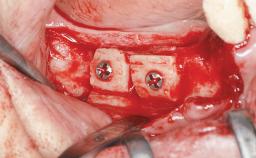

Ridge Preservation and Implant Placement for a Fixed Dental Prosthesis After a Car Accident

It is well known to clinicians that any removal of teeth will, over time, cause the dimensions of the alveolar ridge to be reduced by resorption of the bundle bone and by changes related to external modeling. This development is particularly evident in the crestal region with its thin buccal bone that consists of bundle bone almost entirely. The facial bone will rapidly resorb as blood supply from the periodontal ligament gets disrupted (Araújo and Lindhe 2005). There is no reason why traumatic tooth loss should not have the same consequences. It takes more than achieving implant osseointegration for a treatment outcome to be considered successful. No deficiency of bone or soft tissue is acceptable when an ideal esthetic outcome is the goal. Several articles (Sanz and coworkers 2011; Vignoletti and coworkers 2011) have reported on techniques of improving the alveolar ridge for implant treatment, notably focusing on protecting tissues from resorption.

Bone Augmentation Horizontal|Simultaneous|Sinus Floor Elevation|Staged

Augmentation Materials Xenogenous|Membrane

Bone Volume Deficient vertically or deficient vertically AND horizontally